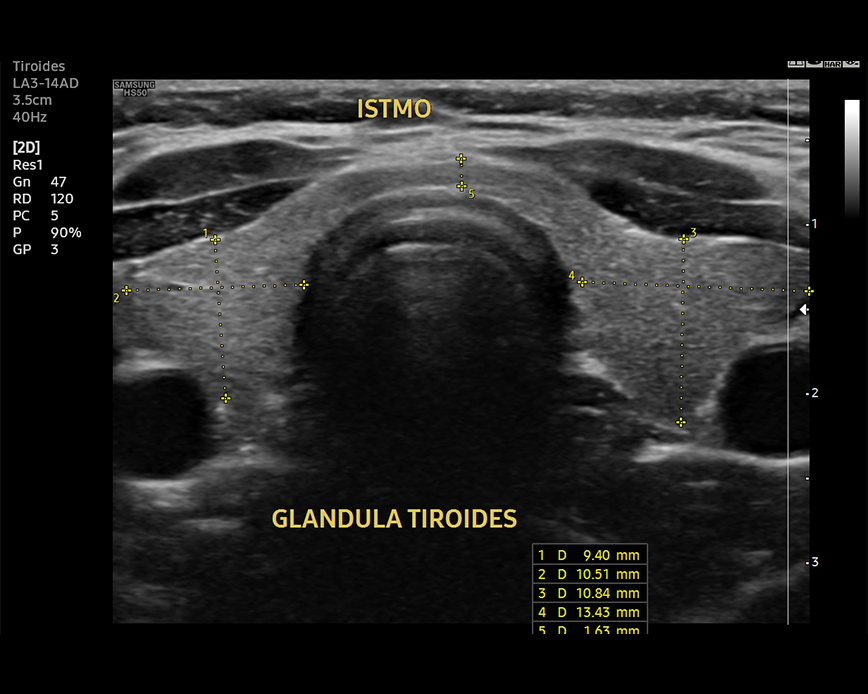

Ecografía de Tiroides

- nódulos tiroideos

- bocio(agrandamiento de la tiroides)

- evaluación de masas cervicales

- disfunción tiroidea: híper e hipotiroidismo

- cáncer de tiroides